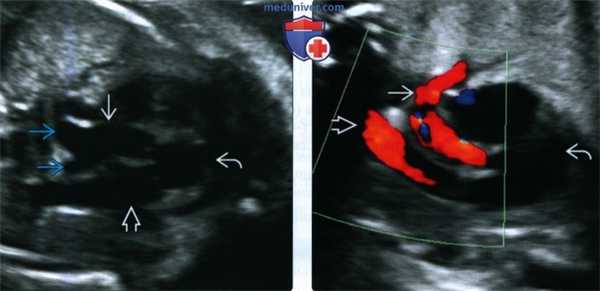

2. УЗИ при гетеротаксическом и кардиоспленическом синдроме у плода:

• УЗИ в режиме серой шкалы:

о ЛПИ: перерыв нижней полой вены:

- Вены печени впадают непосредственно в предсердие

- Непарная вена (продолжение нижней полой вены) расширена, находится позади аорты

о ППИ: нижняя полая вена и аорта находятся по одну сторону от позвоночного столба, при этом нижняя полая вена лежит кпереди от аорты

о Двусторонняя верхняя полая вена:

- Характерно для ЛПИ и ППИ

о Нарушение локализации желудка:

- Справа, слева или по центру в зависимости от расположения печени

о Смещение печени к средней линии

о При ЛПИ может отсутствовать желчный пузырь

• ЦДК:

о Находят селезеночную артерию:

- При полисплении (ЛПИ) сохранена

- При асплении (ППИ) отсутствует

о Находят и отслеживают ход вен большого круга кровообращения и легочных вен